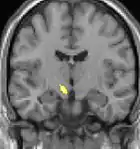

|  |  |  |

| La tomographie par émission de positons (TEP) montre les zones du cerveau étant activées durant la douleur | ||

| La morphométrie voxel par voxel (VBM) montre les différences structurelles des zones du cerveau | ||

Les images par tomographie à émission de positron indiquent les régions du cerveau qui sont activées lors de la douleur, par rapport aux périodes sans douleur. Elles montrent les régions du cerveau qui sont toujours actives durant la douleur en jaune/orange (appelé "matrice-douleur"). La zone au centre (dans les trois vues) est spécifiquement activée uniquement pendant la crise. Les photos sur la ligne du bas (effectuées par VBM) montrent les différences structurelles entre les patients souffrant d'AVF et des personnes saines : seulement une partie de l'hypothalamus est différente[50],[51].